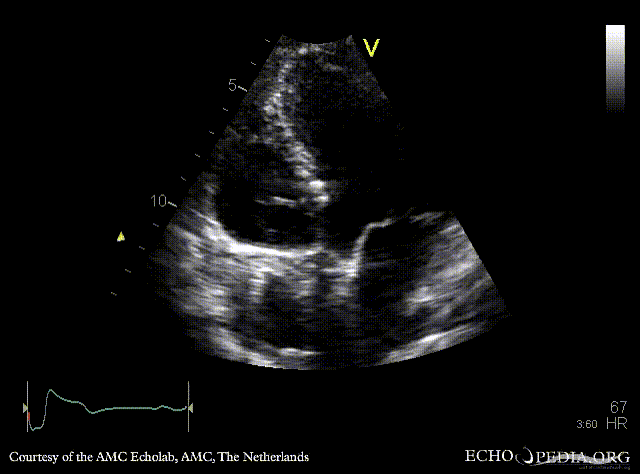

Tricuspid valve stenosis

Courtesy of: AMC Echolab, AMC, The Netherlands

A4CH: doming of tricuspid valve leflets, pacemaker lead in situ Continuous-wave Doppler signal of transtricuspid flow